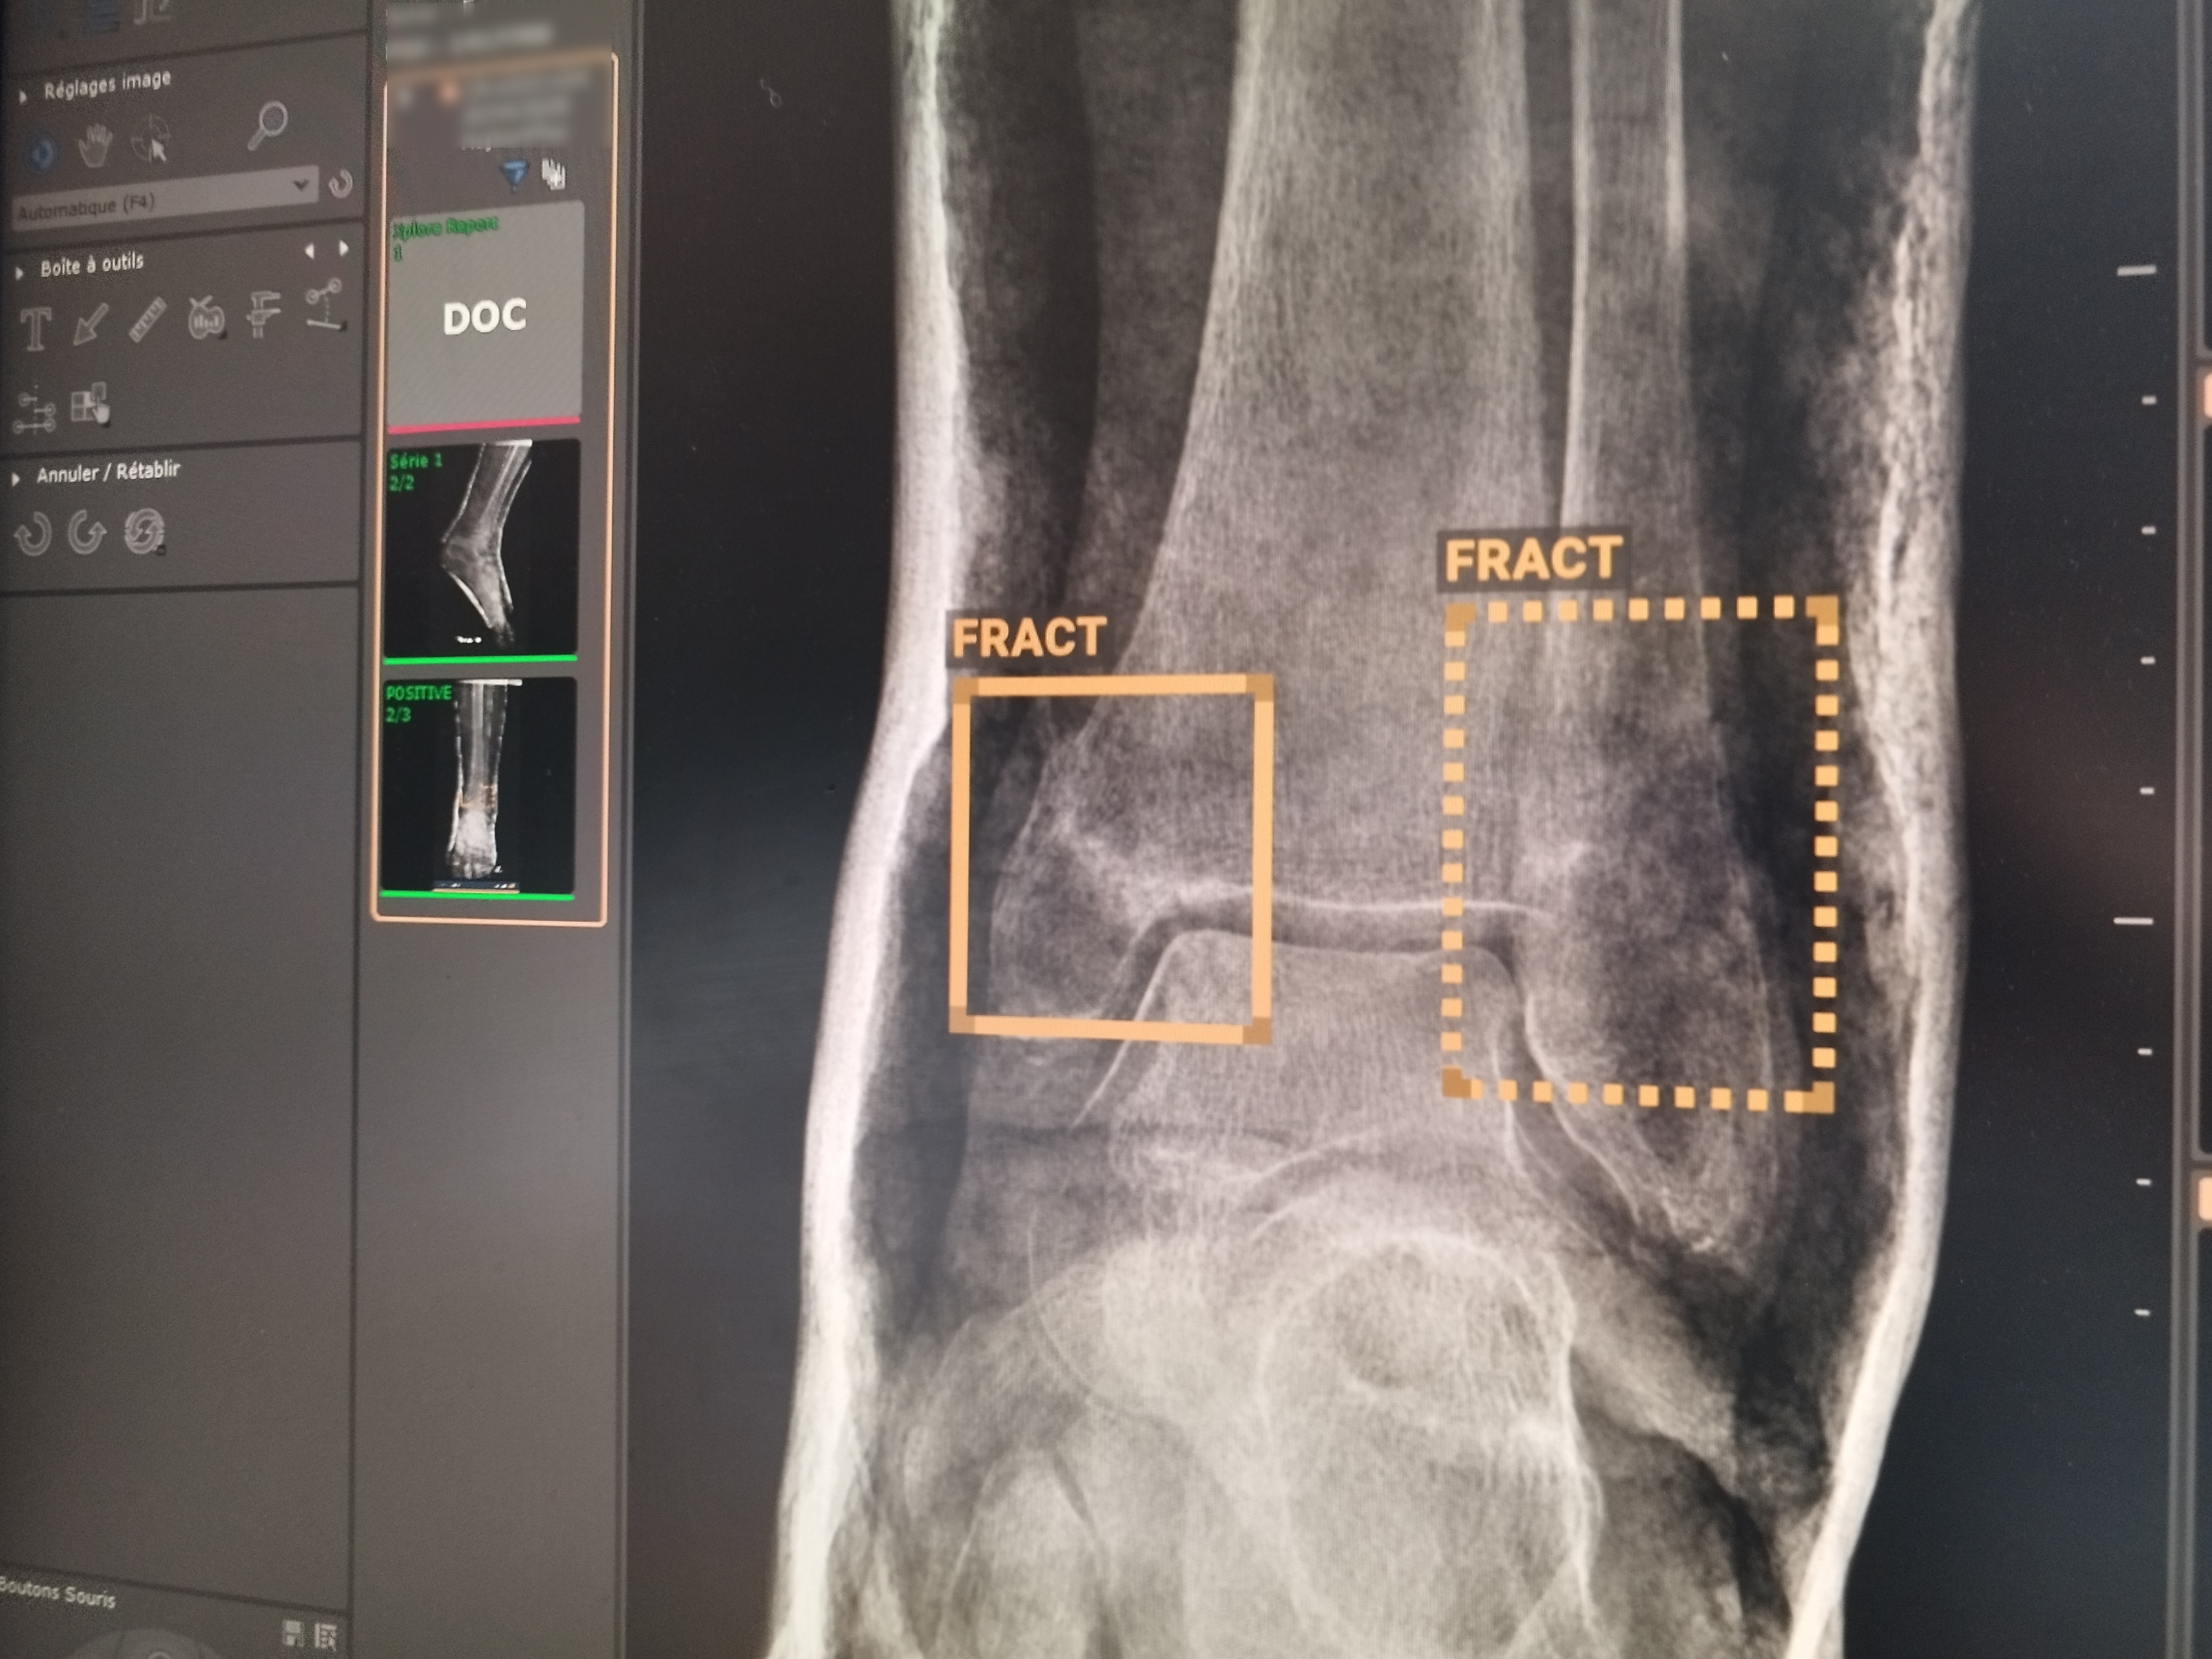

Le Dr Stéphane Pages, responsable du service imagerie de la clinique de l'Ospedale, présente l'aide à l'interprétation apportée par l'IA sur une suspicion de fracture.

Sur la radio, à l’oeil nu, on observe un trait blanc qui traverse le bas d’un tibia. Le radiologue est formel, l’IA aussi : « Fracture », suspecte-t-elle, encadrant en orange la zone en question. Toujours sur l’os, mais sur une autre zone, l’IA dessine un deuxième carré, celui-ci en pointillés. « Ca veut dire qu’il y a un doute », explique Stéphane Pages, cadre de santé en imagerie à la clinique de l’Ospedale.

Un carré continu et l'IA est formelle : il y a fracture. Un carré en pointillés, c'est quand l'IA a un doute.